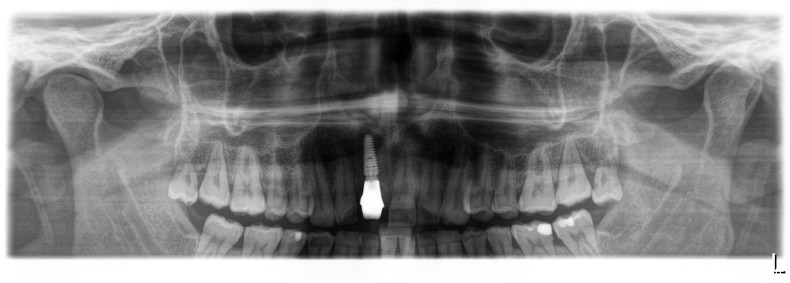

Neben patientenbezogenen und chirurgischen Faktoren spielt dabei auch das Implantatdesign eine wesentliche Rolle. Die vorliegende Falldokumentation zeigt eine Sofortimplantation Regio 11 mit digitaler Planung anhand von DICOM- und STL-Daten. Die präoperative Planung erfolgte softwaregestützt, die Implantatposition wurde prothetisch orientiert festgelegt. Klinisch und radiologisch lagen günstige Ausgangsbedingungen für eine Sofortimplantation mit Sofortversorgung vor.

Postoperativ kam es trotz korrekter Implantatpositionierung und regelrechter Sofortversorgung zu einer Fraktur des Implantatkörpers im Bereich der Implantatschulter. Die radiologische Diagnostik mittels Röntgen und DVT zeigte ein Aufplatzen des Implantats im Übergangsbereich zwischen Konusverbindung und Implantatplattform. Das Frakturmuster deutete auf eine strukturelle Überlastung im hoch beanspruchten Schulterbereich hin. Implantatfrakturen stellen insgesamt eine seltene, jedoch für Patient und Behandler belastende Komplikation dar. Sie treten bevorzugt in Regionen mit erhöhten Biege- und Querkräften auf, insbesondere in der Frontzahnregion und bei frühzeitiger funktioneller Belastung.

Nach Entfernung des frakturierten Implantatkörpers erfolgte eine erneute Sofortimplantation mit einem alternativen Implantatdesign. Begleitend wurden Maßnahmen zur Stabilisierung von Hart- und Weichgewebe durchgeführt.